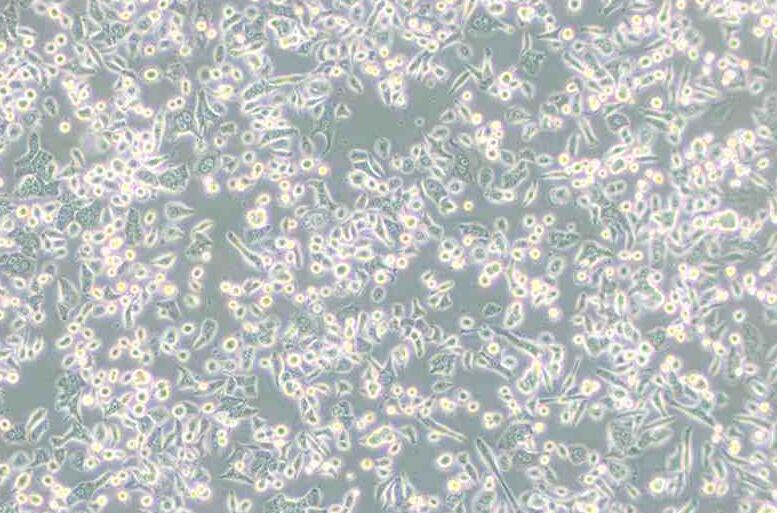

细胞形态:

上皮细胞样

细胞形态上皮细胞样